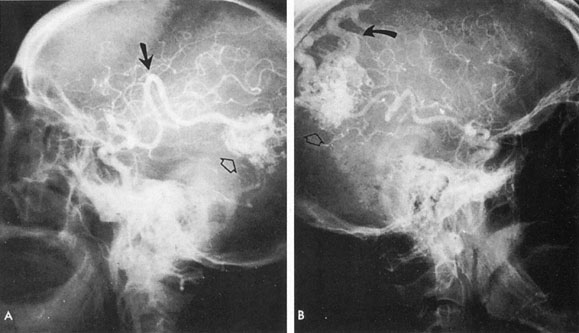

The therapy for AVMs has been reviewed elsewhere.91–93 The preferred treatment remains complete surgical excision of the malformation. However, significant advances in endovascular and radiosurgical techniques have resulted in a marked increase in the use of multimodal, staged approaches to AVM treatment. A variety of intravascular techniques use embolization91 with materials such as particles of polyvinyl alcohol (PVA), platinum coils, and injection of liquid N-butyl-cyanoacrylate (NBCA) adhesive (Fig. 11). Complications of intravascular embolotherapy include vessel perforation by the catheter, migration of embolic materials, and infarction and hemorrhage of normal brain.

Fig. 11. Embolization of middle cerebral vessels that supply occipital lobe arteriovenous malformation (AVM). The patient had a subarachnoid and intraparenchymal hemorrhage that produced a left homonymous field defect. A: Right carotid arteriogram demonstrates contribution via posterior communicating artery to a right occipital lobe AVM. B: Vertebral injection. The arrow points to the enlarged right posterior cerebral artery that is a major feeder of the AVM. C: Right carotid arteriogram during glue embolization procedure. The arrow points to a catheter as it traverses the segment seen in (B). The catheter was advanced via the internal carotid artery but is positioned far posteriorly. D: Upper branches to the AVM now are occluded, with residual low-flow vascularization via the middle cerebral artery. E: Skull film showing radiopaque glue within the AVM and blood vessels previously supplying it. The patient had a persistent visual field defect but greatly reduced headache and no persistence of subjective bruit. (Courtesy of Dr. Joseph Horton.)